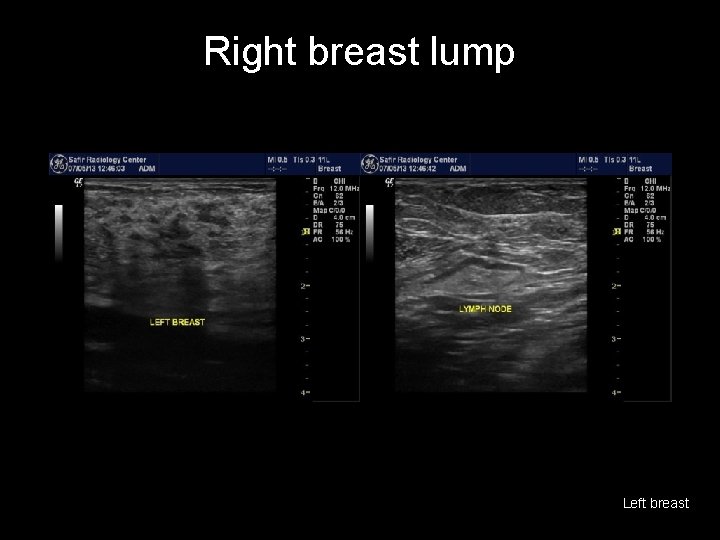

Right breast lump Left breast

Right breast lump • • irregular mass, hypoechoic, with heavy post acoustic shadowing and hypervascularity the lymph nodes appear reactionary with preserved sinus BREAST CANCER (BIRADS V) http: //radiopaedia. org/cases/breast-cancer-7